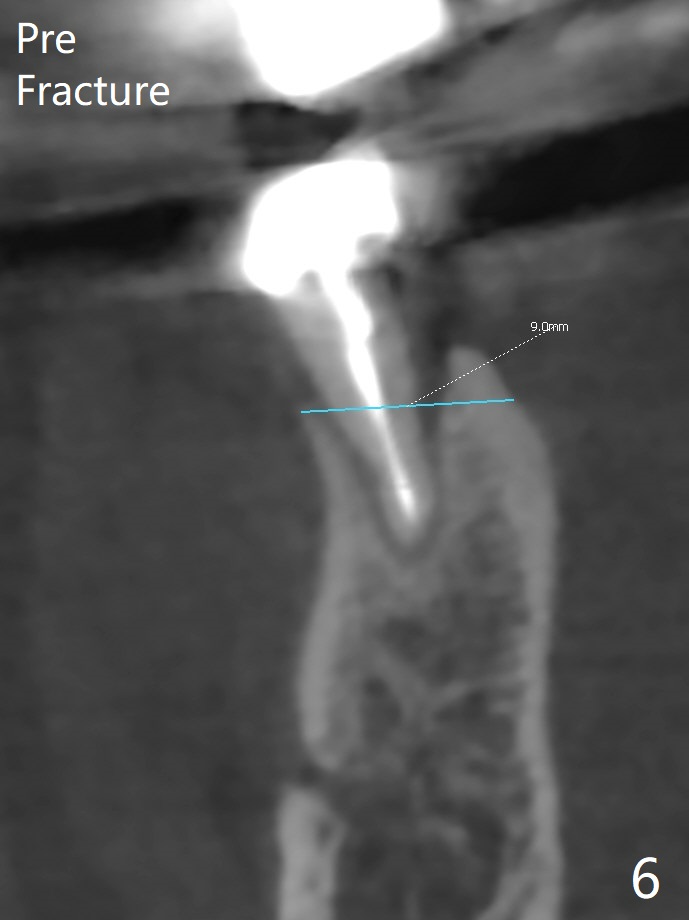

A 77-year-old woman agrees to have the lower right 2nd premolar extracted after lengthy delay (Fig.1,2 buccolingual plate present, but low) and grafted (Fig.3 *).  Cortical graft is heavily packed, covered by a small piece of 6-month membrane and sutured with 4-0 Chromic gut suture.  The socket is closed 7 days postop (Fig.4).   The buccal plate seems to have been reformed 6 months postop (Fig.5,7, as compared to Fig.6 (pre-fracture)).  Return to No Deviation Surgery  Xin Wei, DDS, PhD, MS 1st edition 08/19/2020, last revision 05/12/2021